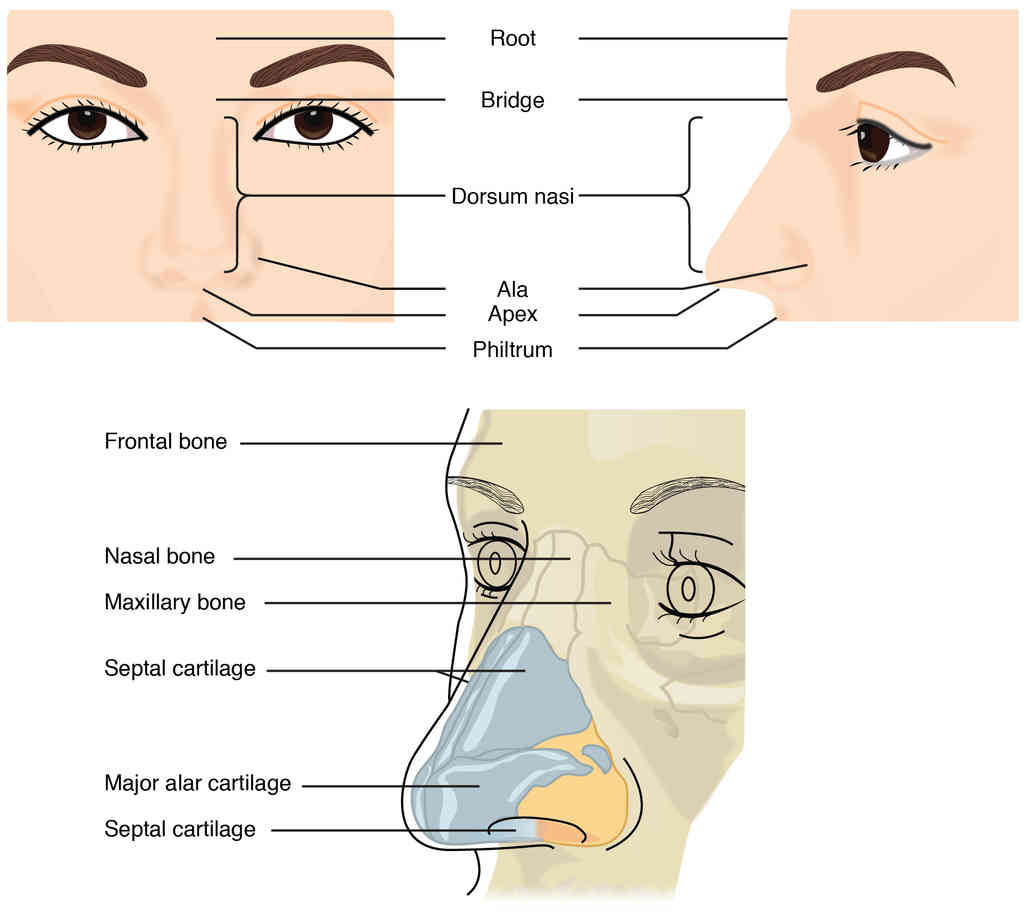

This page is under construction. For now, it is just a resource of the images found in the OpenStax Anatomy and Physiology Handbook. It wil slowly change into a revision tool. Each slide has a number. Use this to refer to the slide. When completed, it will have an unlabelled section, with labelled slides in parallel. On the unlabelled slides, write your answer and use the labelled slide to assess yourself. Keep track by also noting the number on each slide. Improvement at each attempt is important, more so than full marks on a first attempt.